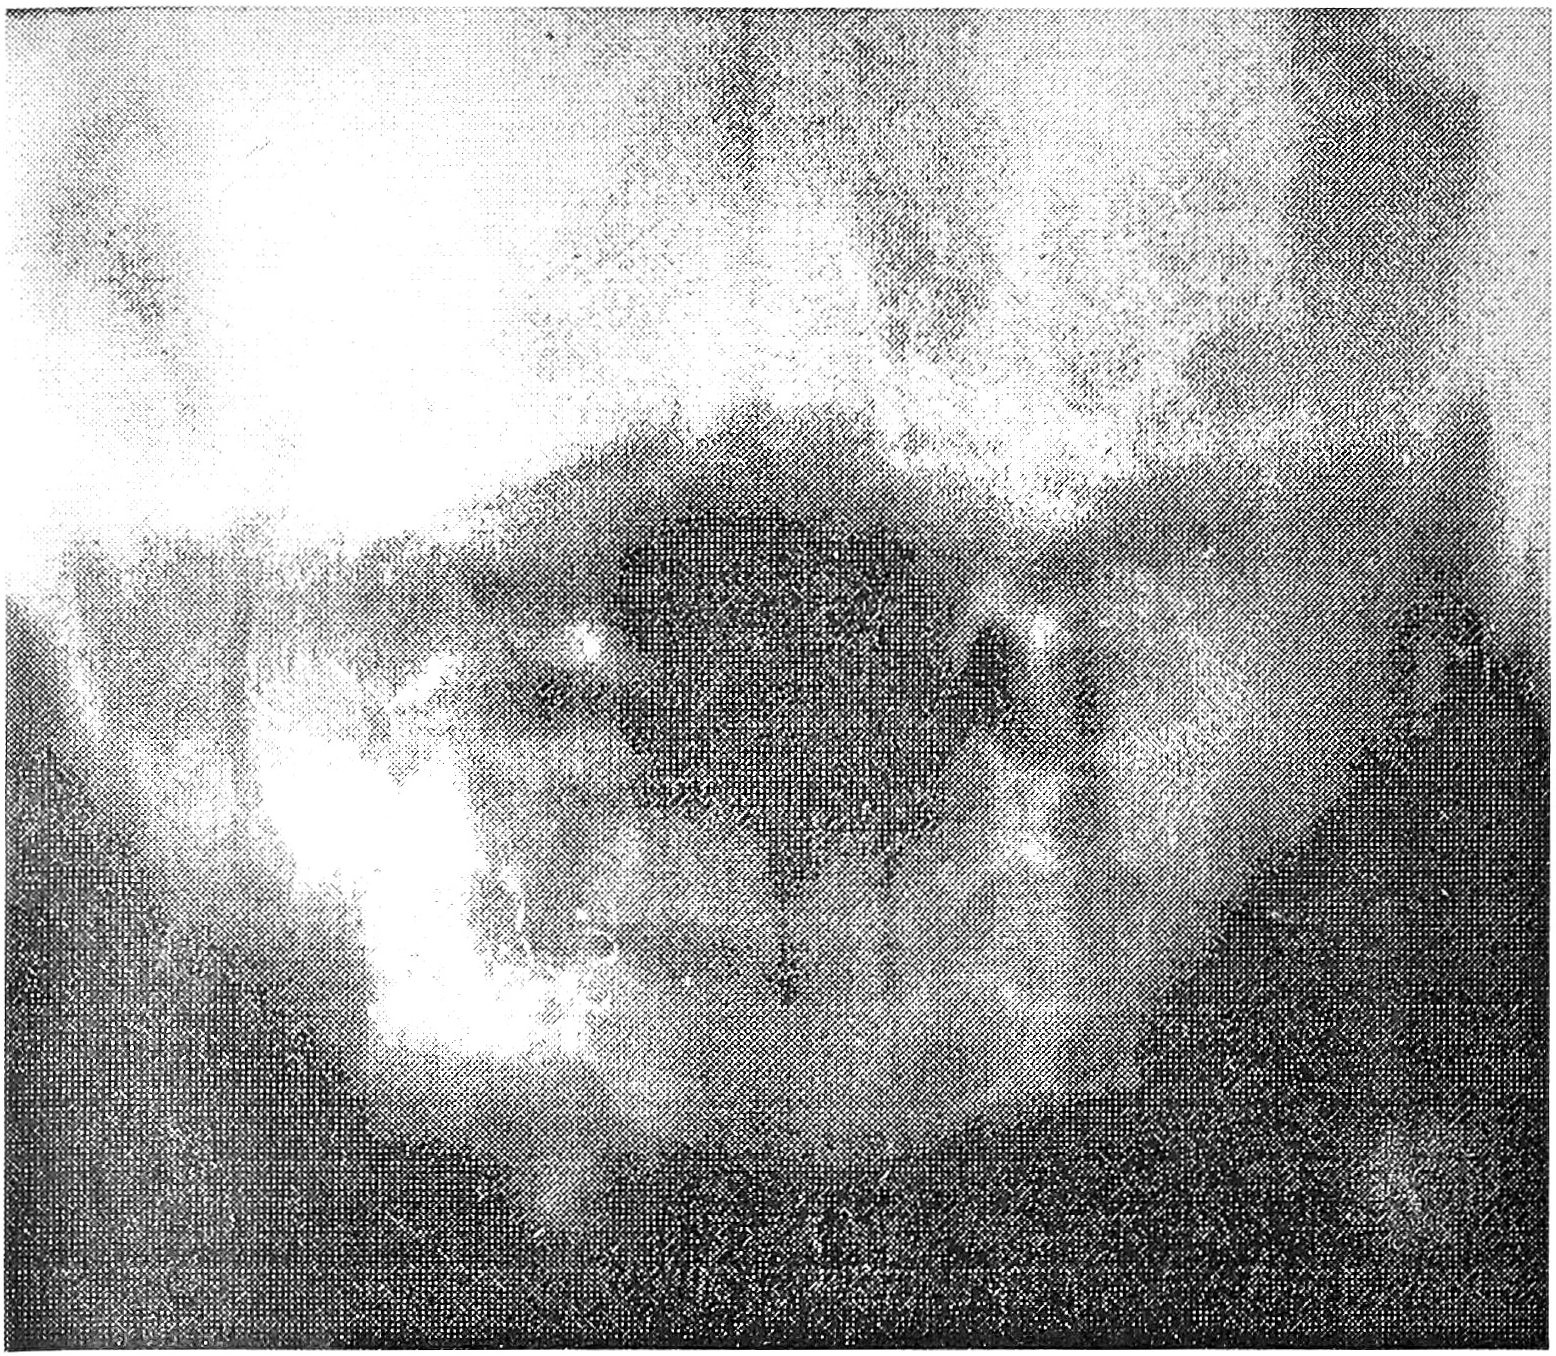

В 2 случаях коронарная компьютерная томография позволила выявить аномалию развития верхнешейного отдела позвоночника: в одном — ассимиляцию атланта с затылочной костью, в другом — сращение С1 и С2 позвонков (см. рис. 3 на вклейке).

Рис. 3. Коронарная компьютерная томограмма больной с аномалией развития верхнешейного отдела позвоночника: видны сращение атланта с мыщелками затылочной кости, деформация зубовидного отростка, неправильная форма боковых масс атланта, разный уровень расположения боковых атлантоаксиальных суставов.